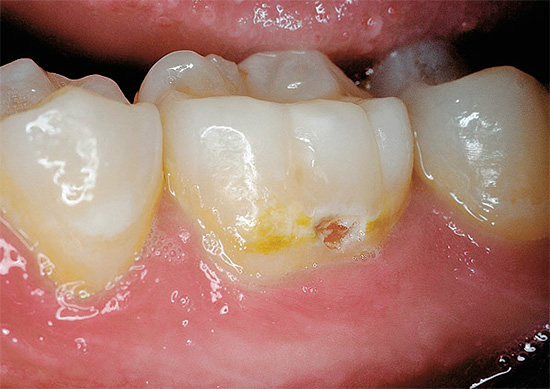

E poi - l'aspetto delle aree cariate dopo che il foro passante si è formato nello smalto e la dentina ha iniziato a fallire:

La sconfitta della dentina segna l'inizio della fase della carie secondaria.

La dentina è molto più porosa e più morbida dello smalto e assorbe facilmente varie sostanze coloranti dalla cavità orale. Ecco perché, dopo l'inizio della lesione, diventa rapidamente scuro.

Sotto l'influenza di fattori cariogeni, la dentina viene distrutta molto più facilmente dello smalto, e quindi lo sviluppo della carie media e la sua transizione verso il decadimento profondo di solito avvengono abbastanza rapidamente.

Con la carie profonda, come suggerisce il nome, gli strati profondi di dentina sono interessati fino alle aree vicino alla polpa. Se la polpa stessa è interessata, la pulite inizia con dolore acuto e il rischio di infiammazione parodontale.